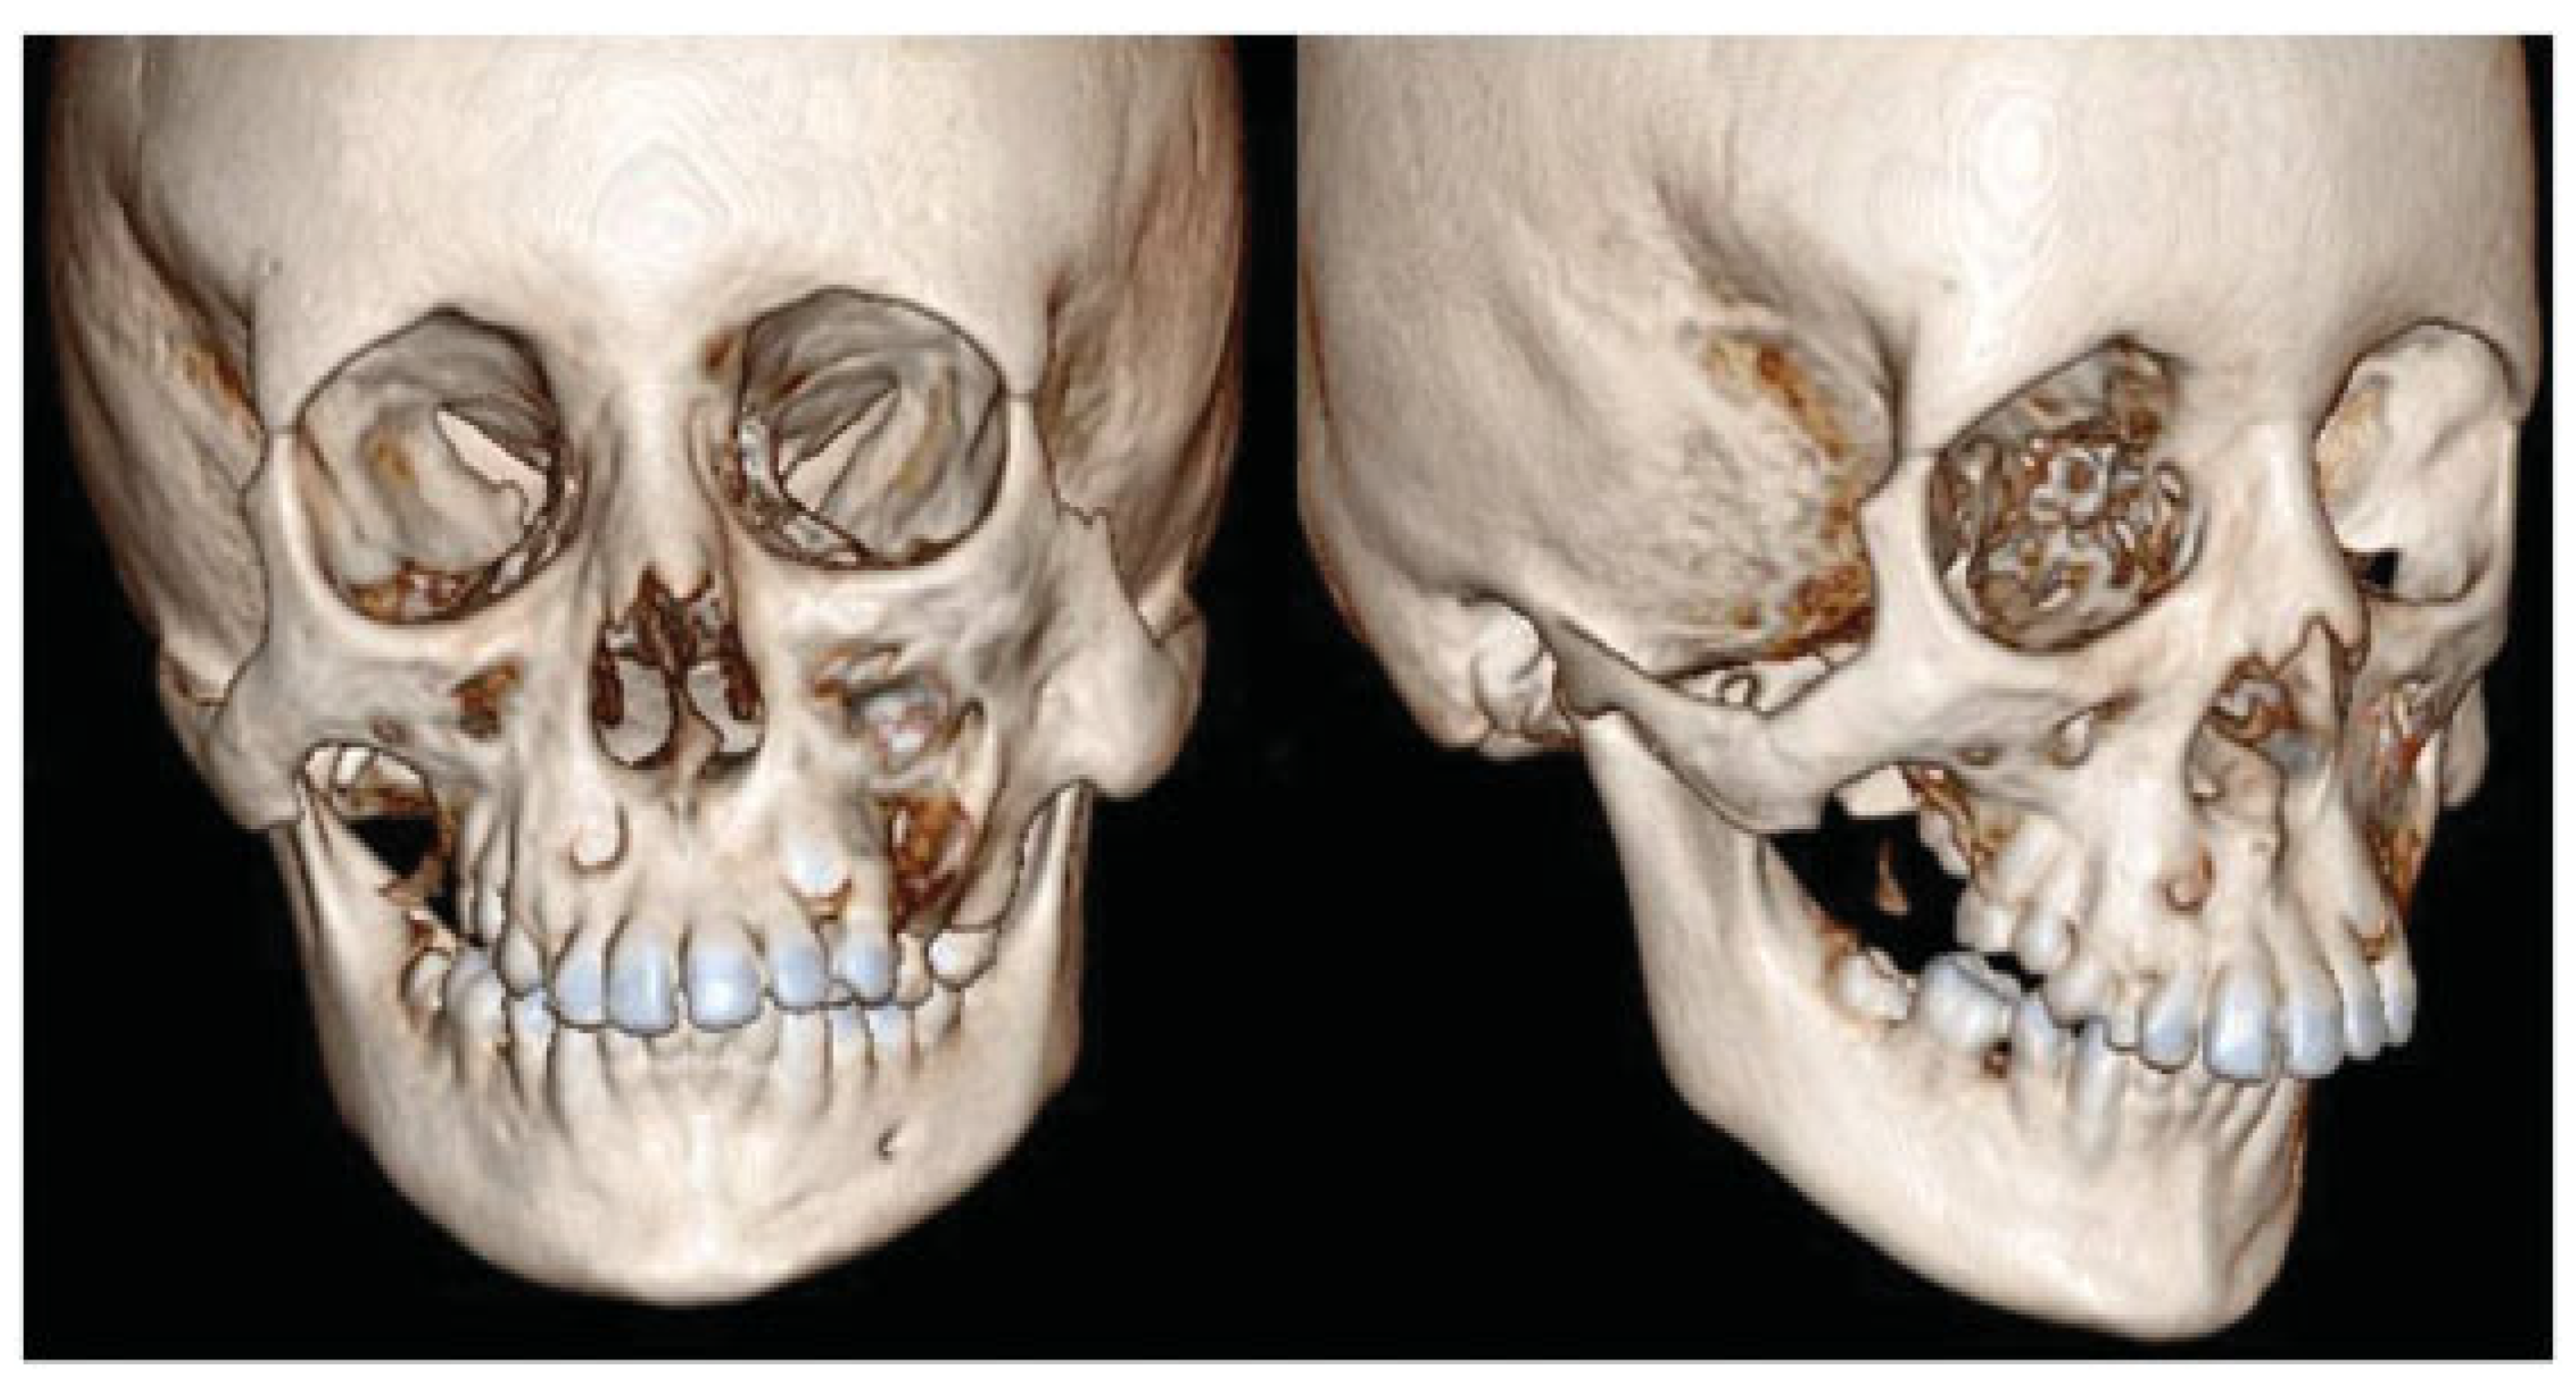

- Incomplete Tessier 7 soft tissue facial cleft and a complete skeletal Tessier 7 cleft on the right side

- Incomplete Tessier 5 skeletal and soft tissue Tessier 6 facial cleft on the left side